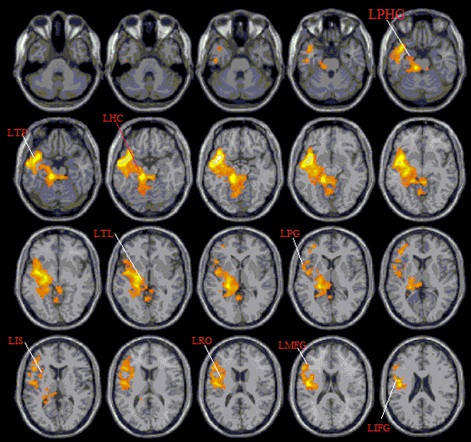

LTP: Left Temporal Pole

LPHG: Left Parahippocampal Gyrus

LRO: Left Rolandic Operculum

LIFG: Left Inferior Frontal Gyrus

LPG: Left Precentral Gyrus

LHC: Left Hippocampus

LMFG: Left Middle Frontal Gyrus

LIS: Left Insula

LTL: Left Thalamus

We previously showed how BR can transiently alter brain wave activity in a specific spectrum with statistical significance [9]. We also used 3T-fMRI on eight participants without (control group) for 5 minutes and with BR effect (experimental group) for another 5 minutes. Figure 5 shows the result of the BR effect under BOLD fMRI on different participants, the locations of brain activation including left temporal pole, left parahippocampal gyrus, left rolandic operculum, left inferior frontal gyrus, left precentral gyrus, left hippocampus, left middle frontal gyrus and left thalamus. Based on this result, we compared the neuroanatomical location of direct brain stimulation to the corresponding ASC with IP (Table 3) [16]. By comparison, we found some common forms of experiences evoked using BR stimulation that mimics electrical brain stimulation are the subjective descriptions of ‘deeper sensorial illusions’ and ‘delusion of unreality and unusualness’. The common descriptions are including auditory illusions, visual hallucinations, somatosensory sensations (e.g., warmth or paresthesia) in various parts of the body, the rotatory sensation of the body parts (eg. head), the illusion of body parts moving, urge to cry, and feeling of unreality, etc (e.g., locomotion, eye and head-turning, body swinging, olfactory sensation, and thrusting). The locations of brain activation explored by both BR and TBS including the temporal pole, parahippocampal gyrus, inferior frontal gyrus, hippocampus, middle frontal gyrus, insula, and thalamus [16,21-22]. To explain the phenomenon of ASC with IP induced by BR, some hypotheses have been suggested to explain, for example, the genesis of visual hallucinations. They could be categorized as: psychophysiological (i.e., as a disturbance of brain structure), psychobiochemical (as a disturbance of neurotransmitters), and psychodynamic (as an emergence of the unconscious into consciousness) [24]. Visual or other hallucinations caused by the effect on cerebral electrical discharge, change of synchronous neuronal activity of the brain, or induction of seizure episode have been described and could be induced by TBS [24-26]. As a method of the complementary and alternative therapeutic method, the possible risk of TBS to induce different hallucination associate with seizure may limit its wide application [27,28]. In the case of the BR effect, there is no single case seizure induction, collected. Together with our previous reports of BR effects on the elevation of specific EEG spectrum and cerebral tissue activations of fMRI, we suggest the phenomenon of BR inducing ASC with IP could also be explained by the similar mechanism of the effects on cerebral electrical discharge and change of synchronous neuronal activity of the brain. Up to now, the clinical application of TBS on different psychiatric and neurological disorders have shown good results on depression, schizophrenia anxiety disorders, obsessive-compulsive disorder, substance or food craving, stroke, Alzheimer's disease and different movement disorders [29,30]. Some of these clinical applications had also reported in our previous reports [9-11,13].

Figure 5: It shows participants received fMRI of 5 minutes without (control group) and another 5 minutes with BR effect (experimental group). Activation m aps depicting the effects of BR (experimental - control) on the areas of brain where the contrasts overlap is shown in orange and yellow.